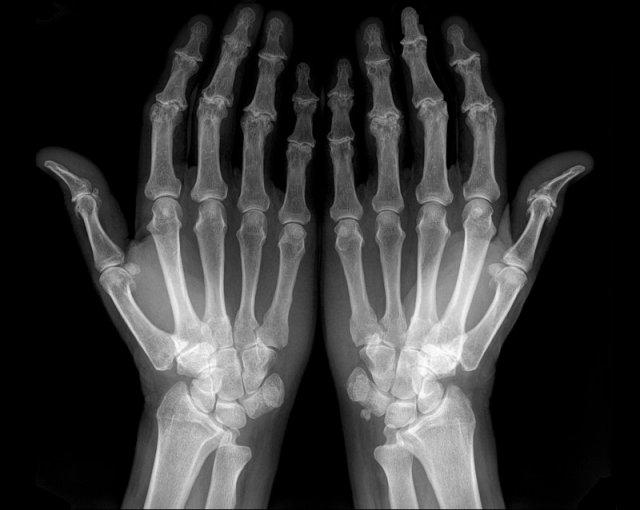

Hình ảnh bào mòn xương vùng rìa điển hình và hẹp khe khớp tại các khớp MCP 3-5.

Lưu ý hình ảnh hẹp khe khớp đồng đều tại các khớp MCP.

Các khớp liên đốt gần (PIP) chỉ biểu hiện hẹp khe khớp tối thiểu.